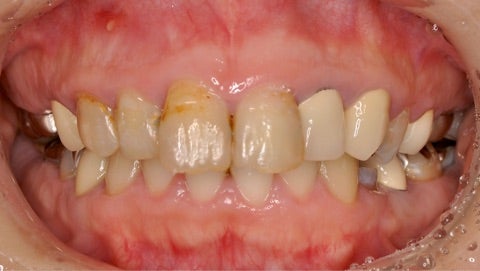

さて、本日は、噛み合わせが悪く、前歯が段々と前に出てきてしまっている事と、全体的に治療が古く、未治療の部分も多くどこから治して良いのか分からない。

▶︎写真ではわかりづらいのですが、前歯の前突に加え、虫歯や不良補綴物による見た目の審美障害を引き起こしています。

また、奥歯の噛み合わせが低く、所謂ディープバイトの状態で、前歯の前突(フレアーアウト)を引き起こしています。

写真左上の歯茎には根尖病巣による膿の出口も確認できます。

今回のケースは審美治療だけでなく、ディープバイトの改善や、保存不可能の部位にインプラント治療も行ったフルマウスの治療計画が必要となりました。